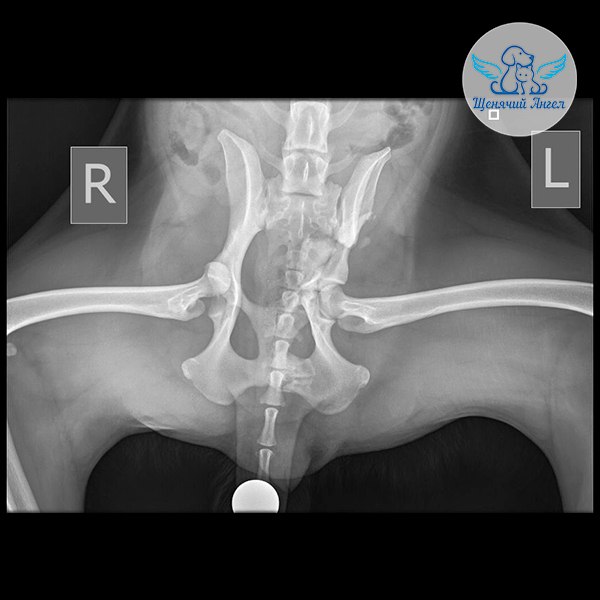

Когда состояние стабилизировалось, мы перевезли Аллочку в Москву на консультацию к хирургу Илье Фёдоровичу Вилковыскому 👨🏻‍⚕️(Ветеринарный центр «МЕДВЕТ»). Рентген выявил комплекс повреждений опорно-двигательного аппарата. На левую переднюю лапу она не может опираться из-за перелома плечевой кости и отрыва надсуставного бугорка лопатки 🥺. Задние лапки также пострадали: справа – вывих тазобедренного сустава, слева – переломы подвздошной, тазовой и лонной костей 😢.

– Правая задняя лапа: требуется резекционная артропластика – удаление головки и шейки бедренной кости.

– Левая задняя лапа: повреждены структуры таза; врач восстановит положение отломков и уже во время операции определит, потребуется ли резекционная артропластика или реконструкция суставной впадины ☝🏻.